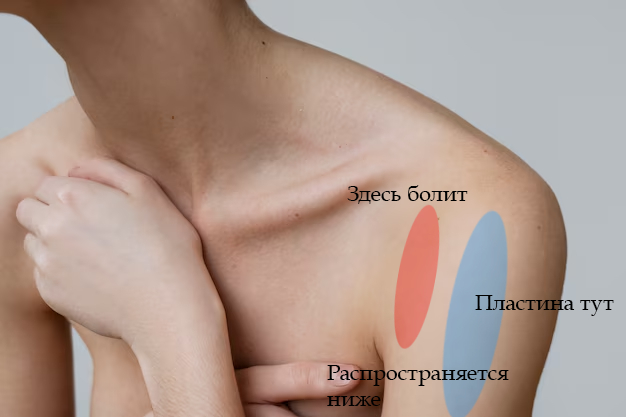

Для ЛЛ и тех, кто не в теме: после ДТП огреблась монтажом костей плеча на пластине и лютыми болями в руке на длительное время. Офигев до края от боли, искала решение проблемы сама, под вопросом была необходимость перемонтажа, нейрохирургии и прочих плюшек. Всё закончилось пока хорошо.

Врач-нейрохирург, специализирующийся на подобных случаях, пересмотрел полученные изыскания и проверил работоспособность конечности. Вердикт был суров - ситуация тяжёлая, но поправимая. Вся рука функционирует отлично, даже с учётом двух месяцев в повязке. Сустав в плече работает плохо, потому что разрабатывать его не даёт боль, но лучше починить старое, чем потом привинчивать новое. Пилюльки для снятия нейропатической боли прописаны правильные, но дозировку нужно больше раза в два. Плюс добавить антидепрессанты, которые так же работают со снятием боли, пусть даже будут жёсткие побочные эффекты. И быстренько разрабатывать руку, как только боль немного спадёт. Разработаю руку - победю. Пожалею себя - будут плохие последствия.

Диагноз невропатолога Комплексный регионарный болевой синдром подтверждён. Руку не отрезаем, нервы не трогаем, посттравматическая нейропатия лучевого нерва под вопросом.